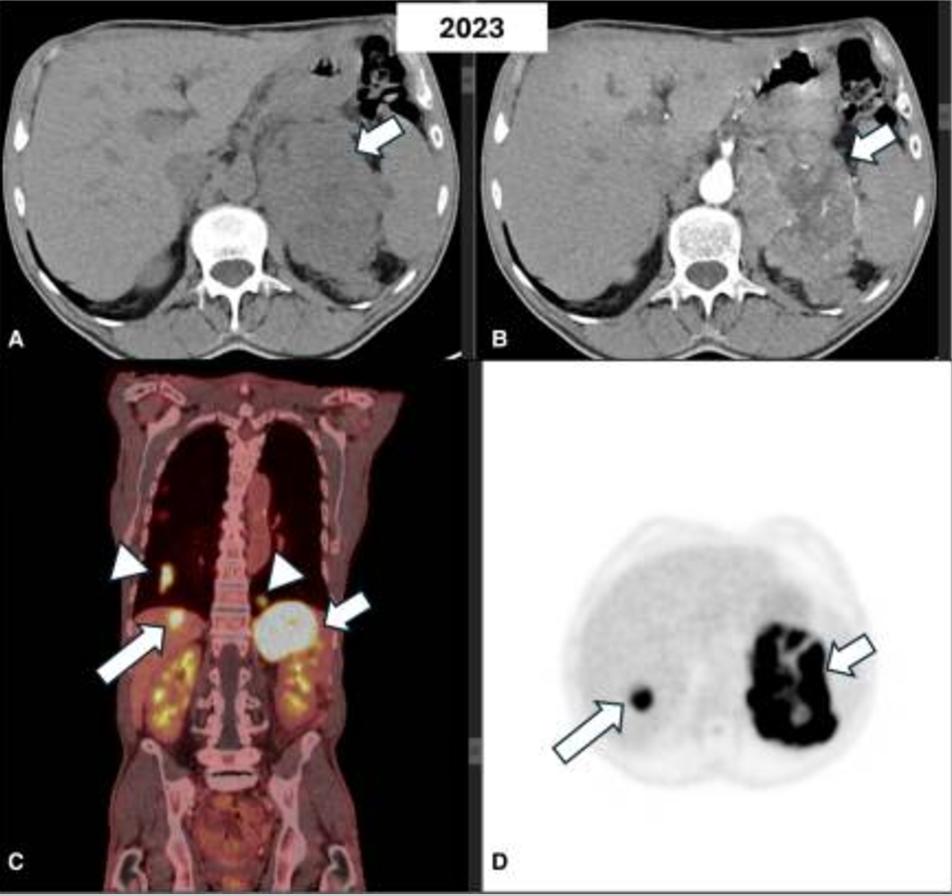

2021年进行的CT扫描显示,病变稳定,为3cm,但非增强衰减值较高,为24HU(图1)。激素筛查显示没有激素分泌过多。2年后,患者在3个月内体重明显减轻,伴有疲劳和腹痛。腹部CT显示,左侧肾上腺存在12×11.5×8.6 cm的异质性病变,表现为周围结构弥漫性浸润(图2)。

图2 同一患者在静脉注射造影剂之前(A)和之后(B)的腹部轴位计算机断层扫描显示,存在一个异质性肿块,中心坏死灶累及左肾上腺并延伸到周围组织(箭头)。在18FDG-PET图像(C-D)上,病变显示18FDG摄取旺盛(小箭头),肝脏(长箭头)和肺部(箭头)出现高代谢活性病变,怀疑有转移

MRI证实存在增大的不均匀左肾上腺肿块,并伴有强烈的对比增强(图3A-3C)。此外,肝脏中描述了2个新的可疑病变,其中1个在第VIII段为2cm,另一个在第VI段为7.7mm,倾向于转移性疾病(图3A-3C)。胸部CT还显示了多个继发性双侧肺部病变(图4A)。18FDG-PET显示,肾上腺病变(18SUVmax)、肝和肺病变(10-12SUVmax)和左肾上腺静脉(12SUVmix)的摄取增加,与血管血栓一致(图2)。